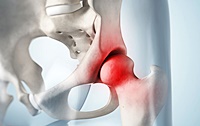

고관절은 골반을 지탱하는 중요한 관절로, 근육과 힘줄로 구성되어 있습니다. 학계에서는 이를 엉덩이 관절이라고 부르며, 신체의 하중을 지탱하는 중요한 역할을 합니다. 고관절은 우리가 정상적으로 서고 움직일 수 있도록 도와주며, 달리기, 점프, 무거운 물건을 들 때 최대 체중의 2~10배에 달하는 압력을 견딥니다. 따라서 적절한 관리가 필요합니다. 오늘은 고관절에서 나타날 수 있는 고관절 통증 증상 10가지에 대해 알아보겠습니다.

고관절 통증의 주요 원인은 퇴행성 질환으로, 나이가 들면서 관절 손상이 발생하는 것입니다. 고관절 자체의 구조적 문제, 주변 근육과 인대의 문제, 척추와 골반 문제 등 다양한 원인이 있습니다. 퇴행성 고관절염, 대퇴골두 무혈성 괴사, 대퇴골 경부 골절, 퇴행성 관절염, 급성 활액막염 등이 주요 원인입니다. 이러한 질환들은 심각한 합병증을 유발할 수 있어 빠른 치료가 필요합니다.